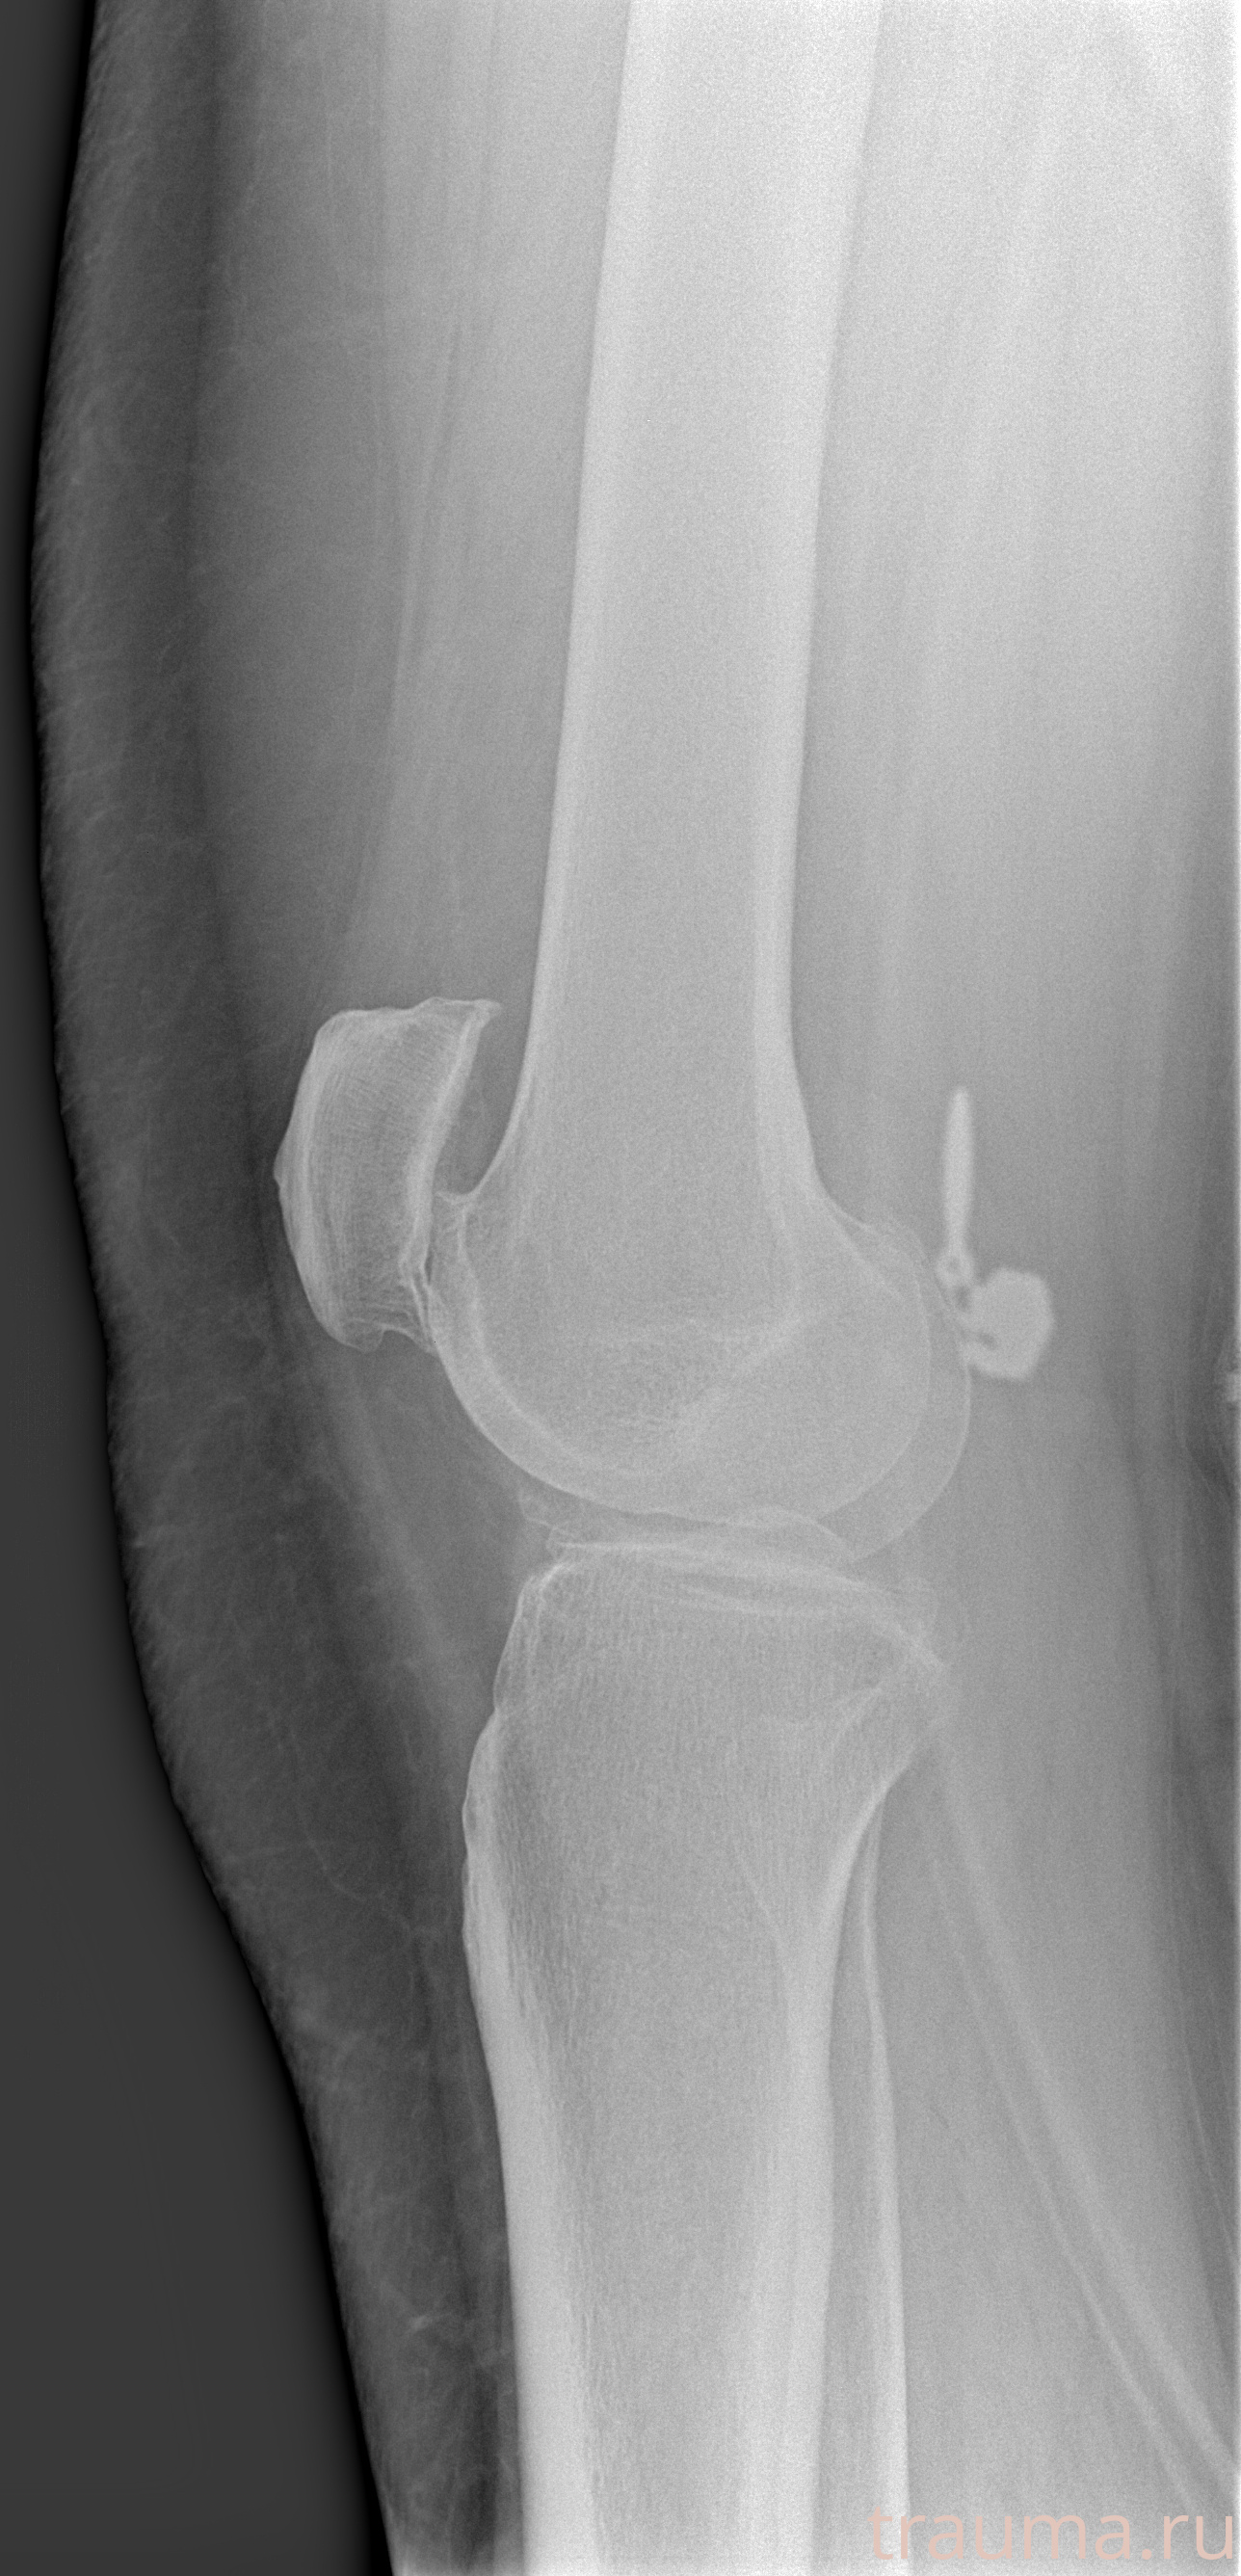

Рентгенограммы